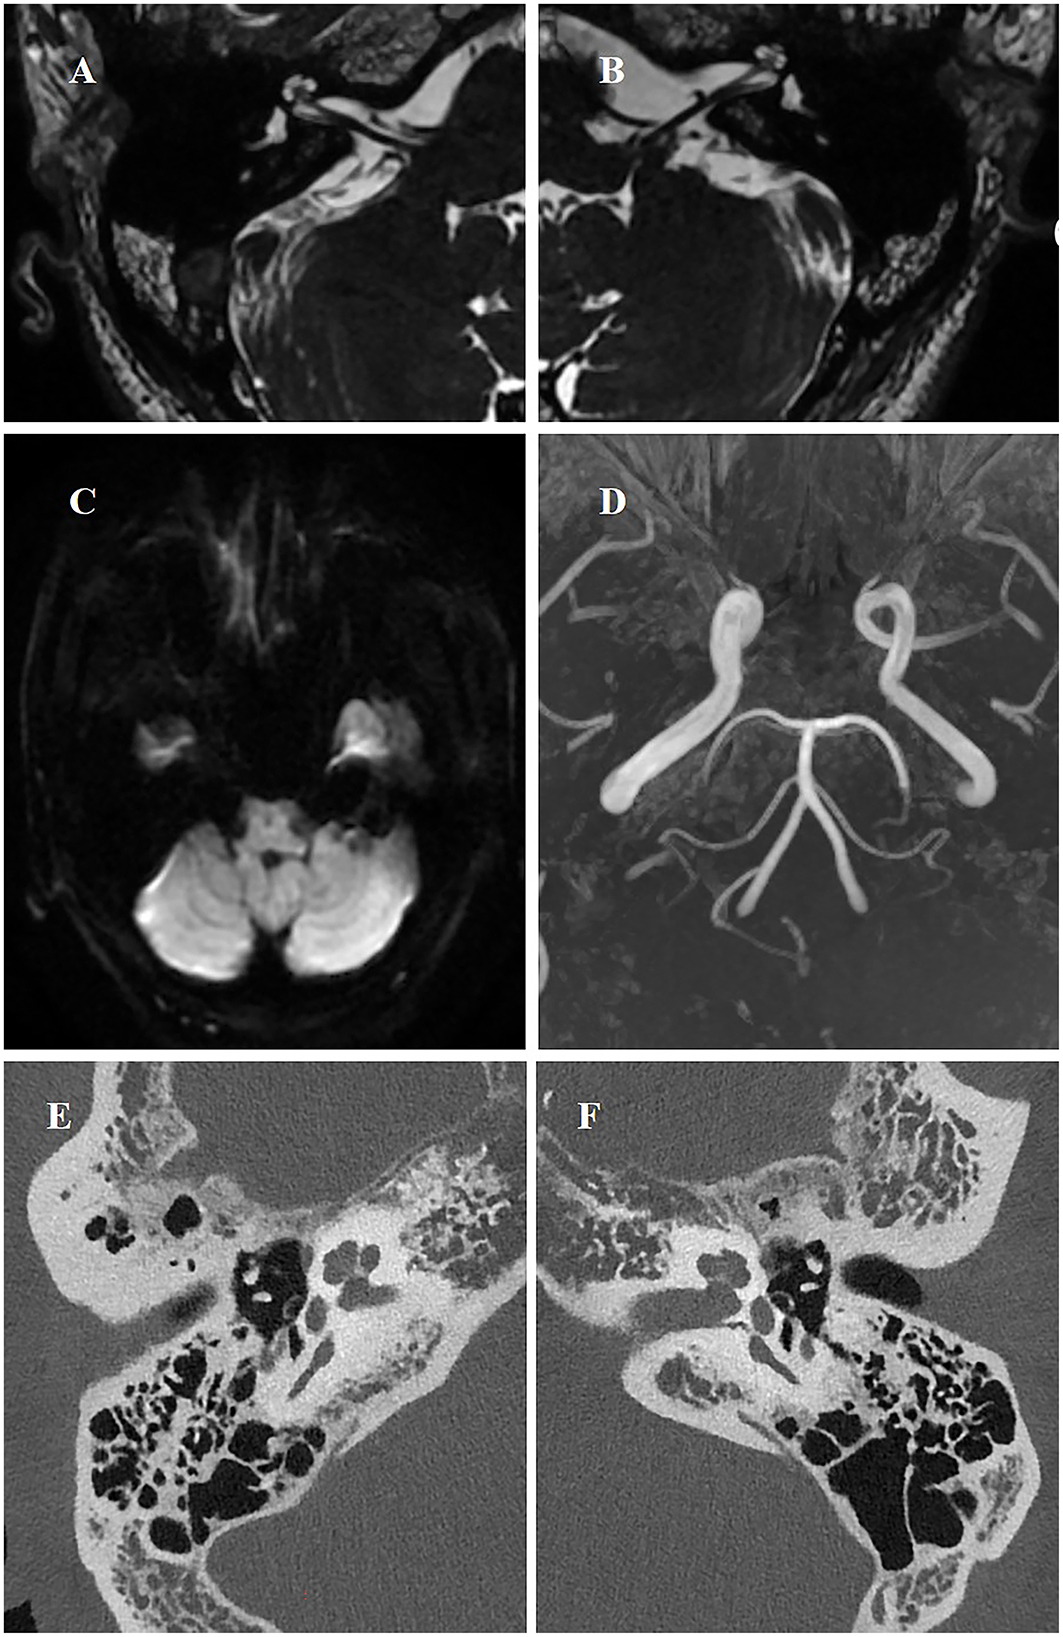

The pathophysiology of idiopathic sudden sensorineural hearing loss (ISSNHL) remains unclear. It is widely hypothesized that vascular ischemia, leading to acute labyrinthine ischemia, may represent the most probable underlying etiology. We describe a 51-year-old previously healthy man presenting with acute-onset left-sided hearing loss, tinnitus, and vertigo persisting for 24 hours. His clinical features were consistent with acute labyrinthine ischemia, suggesting this as the probable etiology of ISSNHL. Initial photon-counting CT (PCCT) of the inner ear suggested that the branches of the anterior inferior cerebellar artery (AICA) supplying the inner ear, including the labyrinthine artery, were slightly attenuated and exhibited a sparse branching pattern. Follow-up imaging after therapy within a week revealed significant improvement in both the vascular caliber and blood flow. To our knowledge, this case represents the first successful application of PCCT to directly suggest acute labyrinthine ischemia, providing the first reported radiological evidence for this mechanism.